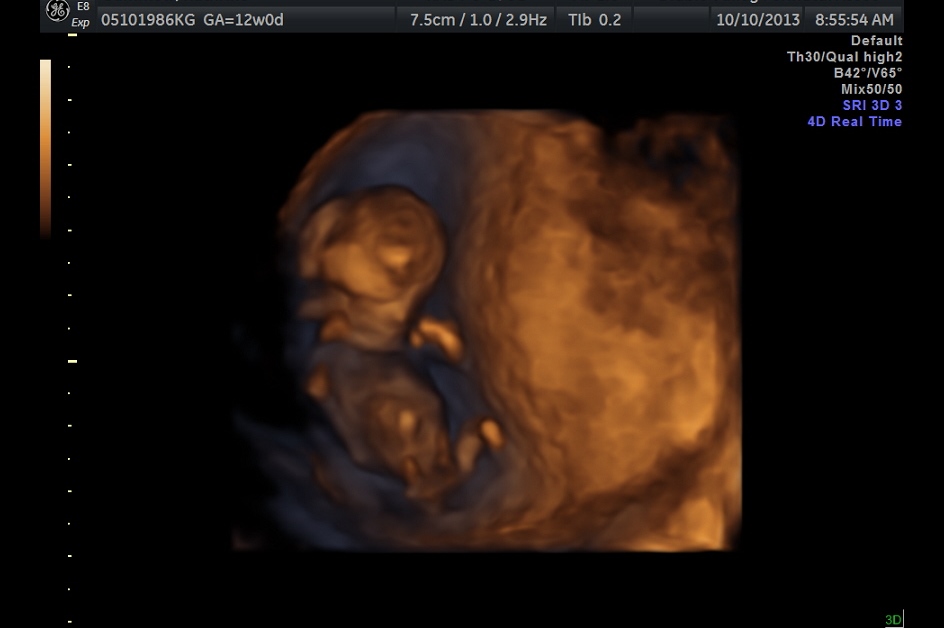

4D pictures from Today's NT Scan

We have two fraternal (yay low high risk pregnancy!) very healthy babies.  Their brains look great, their hearts look great, and they don't seem to be at any risk for Down Syndrome (Going in for blood work tomorrow).  We got to see their long legs and take a good look at arms, hands, and face.  Also we heard their hearts beating for the first time.  Magical.

-First one is baby A, being shy, saying hi and hiding the face

-Third one is the two of them together, baby A is to the right and B is on the lower left.